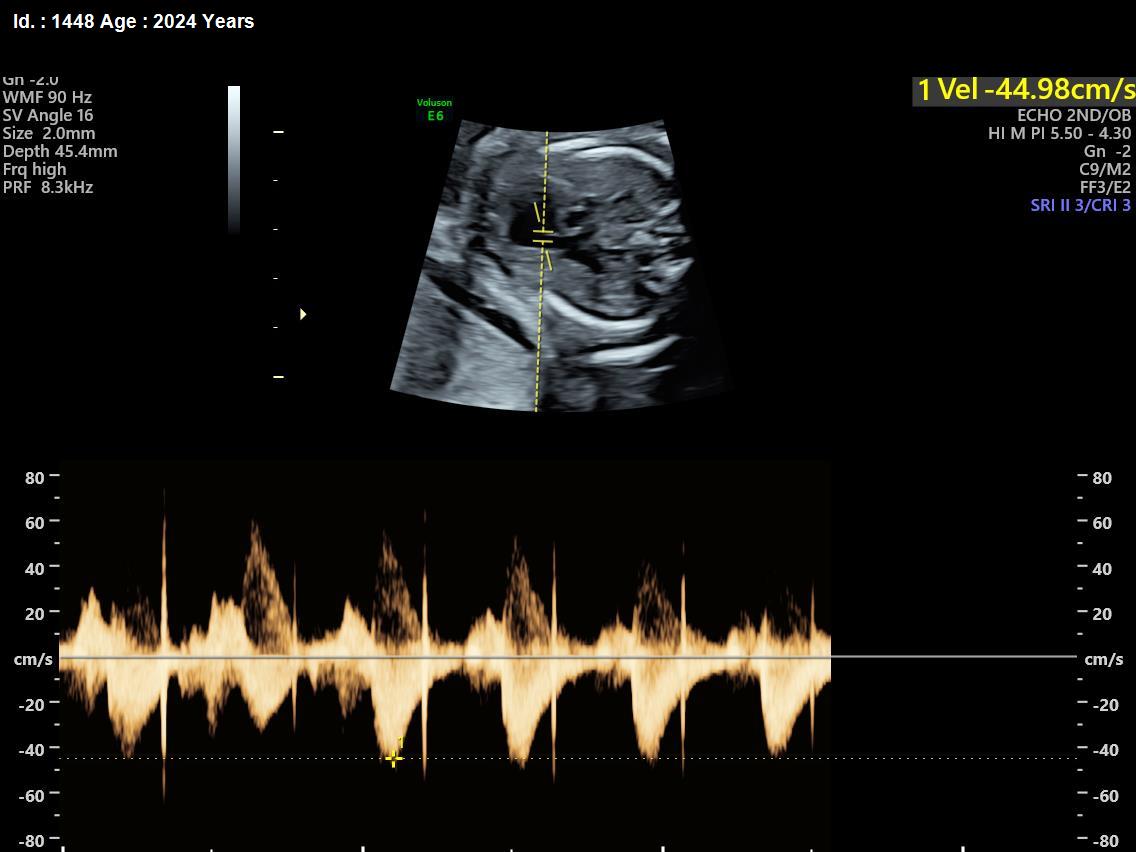

It is a test similar to ultrasound. It allows the doctor to see structure and function of the baby’s heart in detail. It also enables the doctor to see blood flow through fetal heart and cardiac rhythm. The scan is done by a radiologist or a fetal medicine specialist.

A fetal echocardiogram focuses specifically on the fetal heart, providing a detailed examination of its structure and function. In contrast, a standard ultrasound assesses overall fetal development and growth.